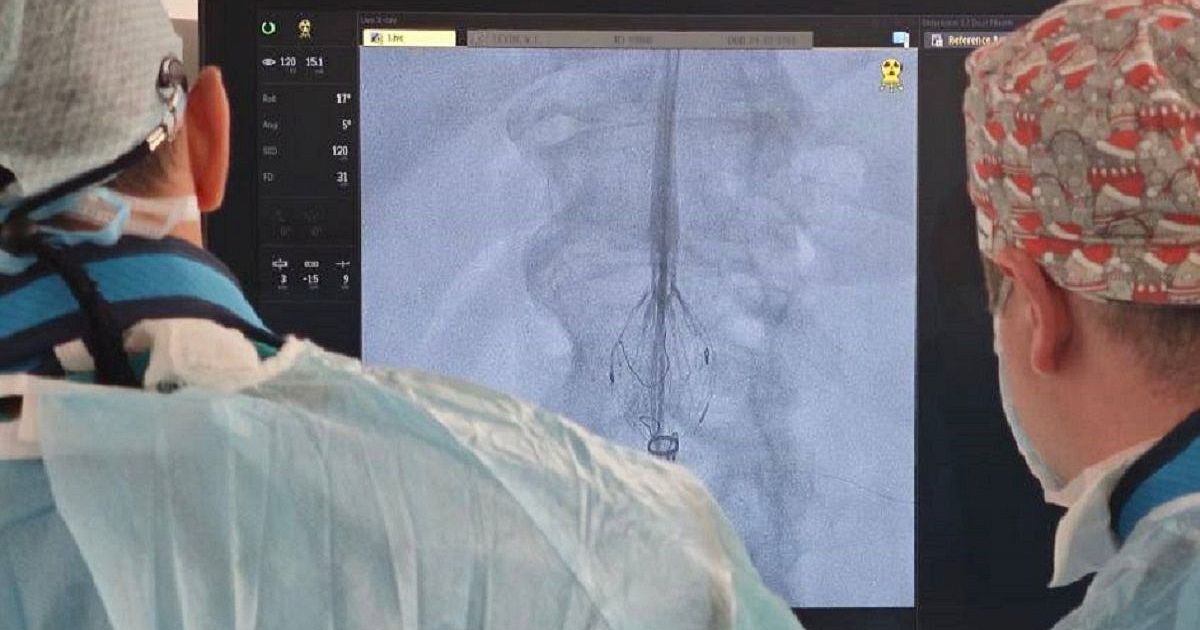

За жизнь 64-летнего мужчины боролись специалисты Краевой клинической больницы №1 вместе с сердечно-сосудистым хирургом из Санкт-Петербурга Алмазом Ванюркиным.

Пациент поступил в НИИ-ККБ№1 с жизнеугрожающим состоянием, ему поставили диагноз — аневризма брюшного отдела аорты с вовлечением почечных артерий. Раньше такую операцию провели бы, вскрыв брюшную полость.

- После проведенной диагностики, врачи приняли решение установить фенистрированный эндографт – специальную конструкцию, предназначенную для восстановления нормального кровотока в сосудах. Эндографт для этого пациента был индивидуально изготовлен на заводе, - сообщил и.о. министра здравоохранения края Евгений Филиппов в своем Telegram-канале.

Он отметил, что такая операция проводилась в краевой больнице №1 впервые, однако благодаря высокой квалификации и богатому опыту Андрея Кузьмина и Владислава Калюжного операция прошла на высшем уровне. Восстановление пациента после такого малоинвазивного вмешательства займет не более двух-трех дней.